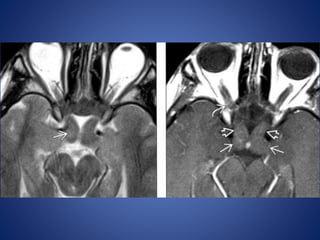

Retinal detachment

Choroidal detachment

Choroidal detachment is accumulation of blood or fluid in supra

choroidal space between choroid and sclera, so collection extend

circumferentially along the entire supra choroidal space ,

configuration is lentiform shaped along medial as well as lateral wall

of globe, choroid bulging medially on either side giving so called

kissing choroid sign.

Anteriorly extend upto ciliary bodies and posterior limit formed by

anchoring effect of short posterior ciliary arteries and nerves

preventing convergence of detached choroidal leaves to a single

point.

Posttraumatic hemorrhagic choroidal detachment

Configuration of collectionis cresent shaped or V shaped on axial sections. Limbs of V represent detached leaves of retina converging towards optic disc represent the apex of V. Collection anteriorly extend upto ora serrata represent anterior limit due to normal anterior attachment of retina. Retinal detachment

Choroidal detachment Choroidal detachmentis accumulation of blood or fluid in supra choroidal space between choroid and sclera, so collection extend circumferentially along the entire supra choroidal space , configuration is lentiform shaped along medial as well as lateral wall of globe, choroid bulging medially on either side giving so called kissing choroid sign. Anteriorly extend upto ciliary bodies and posterior limit formed by anchoring effect of short posterior ciliary arteries and nerves preventing convergence of detached choroidal leaves to a single point.